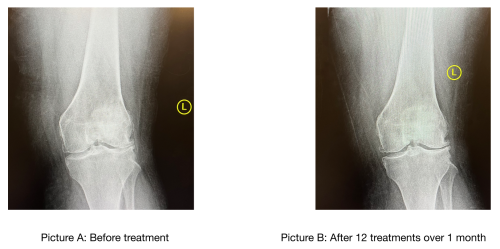

Please refer to the pictures below. The first picture demonstrates a patient on the Knee on Trac. Below the patient, please refer to Picture A and Picture B. Picture A on the left demonstrates a patient with advanced arthritis in her knee PRIOR to implementing therapy with Knee on Trac; Picture B on the right demonstrates xrays of the same patient AFTER 12 visits of Knee on Trac over approximately 1 month time. Please note an increase in disc space on the inner and outer joint spaces noted in Picture B. As a result, the patient is able to go up and down the stairs with greater ease, stand for prolonged time at work, get up from a seated position, and walk with minimal discomfort: